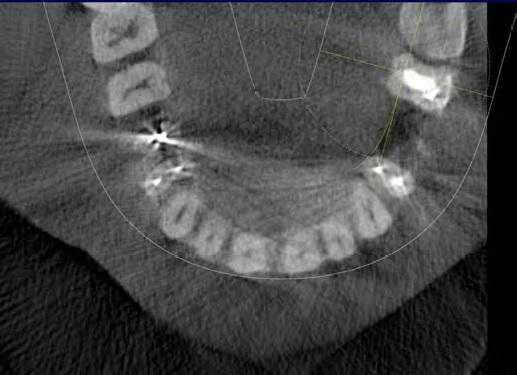

КЛКТ используется в стоматологии начиная с 1981 года. В отличие от обычного КТ, которое создает изображение на разных слоях, КЛКТ создает изображение в 3D пикселях называемых воксель. Так как эти воксели являются изотропичными, объект тщательно измеряется в различных направлениях. Это позволяет визуализировать геометрически неискаженное изображение челюстно-лицевой области, которое возможно просматривать при разных углах. Вдобавок для обеспечения высокого разрешения изображения, КЛКТ доступно для просмотра с разных точек (FOV) для применения в различных ситуациях. В эндодонтии аппарат с ограниченным FOV обычно является достаточным. Обычно, чем меньше объем скана, чем выше пространственное разрешение изображения. Так как ранний симптом периапикальной патологии это прерывистость твердой пластинки и расширение периодонтальной щели, оптимальным разрешением при получении КЛКТ изображения, применяемом в эндодонтии, не должно превышать 200 нм - средняя ширина периодонтального пространства. 3D Accuitomo (K Morita, Corporation, Kyoto, Japan) - первая из малых FOV систем - обеспечивает разрешение в 0,125 мм. Orthophos XG3D (Sirons Germany) также обеспечивает получение FOV 5*5 специально для эндодонтических целей.

Ramamurthy и Matherene описывают ограниченность 2D изображений для определения MB2 каналов (Фото 1).

Фото 1: изображение MB2 в обоих первых молярах

Наиболее частым патологическим состоянием, затрагивающим зубы является воспалительные процессы пульпы и периапикальных областей. Технология КЛКТ теперь предоставляет клиницисту возможность обозревать нужную зону в трех различных плоскостях, тем самым получая 3D информацию. Поражения, заключенные в губчатом веществе кости с малым количеством или отсутствием кортикальной пластинки, на обычной пленке могут быть диагностированы с большим трудом. Lofthag-Hansen, Stavropoulos и Wenzel сравнили точность получаемых данных при КЛКТ с ограниченным FOV и обычными снимками.

Ученые сообщили, что КЛКТ предоставляет более точные диагностические данные (61%) по сравнения с цифровыми (39%) и обычными (44%) рентгенограммами. Но, несмотря на то, что данные КЛКТ являются более точными, исследователи не призывают к полному вытеснению обычной внутриротовой рентгенографии для выявления периапикальных изменений в обычной клинической практике из-за финансовой и вредностной составляющих. Estrela и коллеги предложили использовать периапикальные индексы, основанные на КЛКТ, для идентификации патологий (Фото 4-6).

Фото 4: Периапикальная киста в переднем сегменте нижней челюсти

А: 3D изображение, показывающее большую кистозную полость

B: Изображение секционного распила, показывающее утрату кортикальной пластинки

C: Аксиальный вид, демонстрирующий утрату кортикальной пластинки с лабиальной стороны и интактную пластинку с лингвальной.